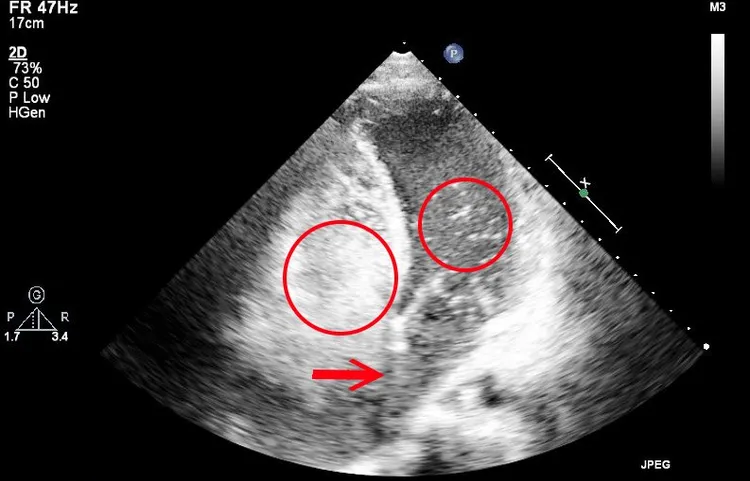

患者氣泡測試超音波顯示,氣泡從阿成右心房中膈缺損(破洞1.5公分)衝到左心房。中國附醫提供

中國醫大附醫專家團隊評估阿成腦內無故長膿,疑與先天性心臟疾病相關,經照會中國附醫兒童醫院兒童心臟科醫師戴以信後續診斷,以「氣泡測試超音波檢查(Bubble test, Agitated Saline Echocardiography)」以及心導管檢查阿成的心臟,發現「心房中隔缺損(Atrial Septal Defect)合併右到左分流」導致他長期慢性缺氧,因右心房的缺氧血逆流進左心房,細菌進而大舉侵入腦部,造成嚴重感染膿瘍再併發水腦,幸好阿成被即時搶救,兒童醫院心臟團隊接續使用「經心導管心房中隔關閉手術」,關閉阿成心臟的先天破洞,防止腦部膿瘍再次發生,術後恢復良好,阿成目前持續復健中。